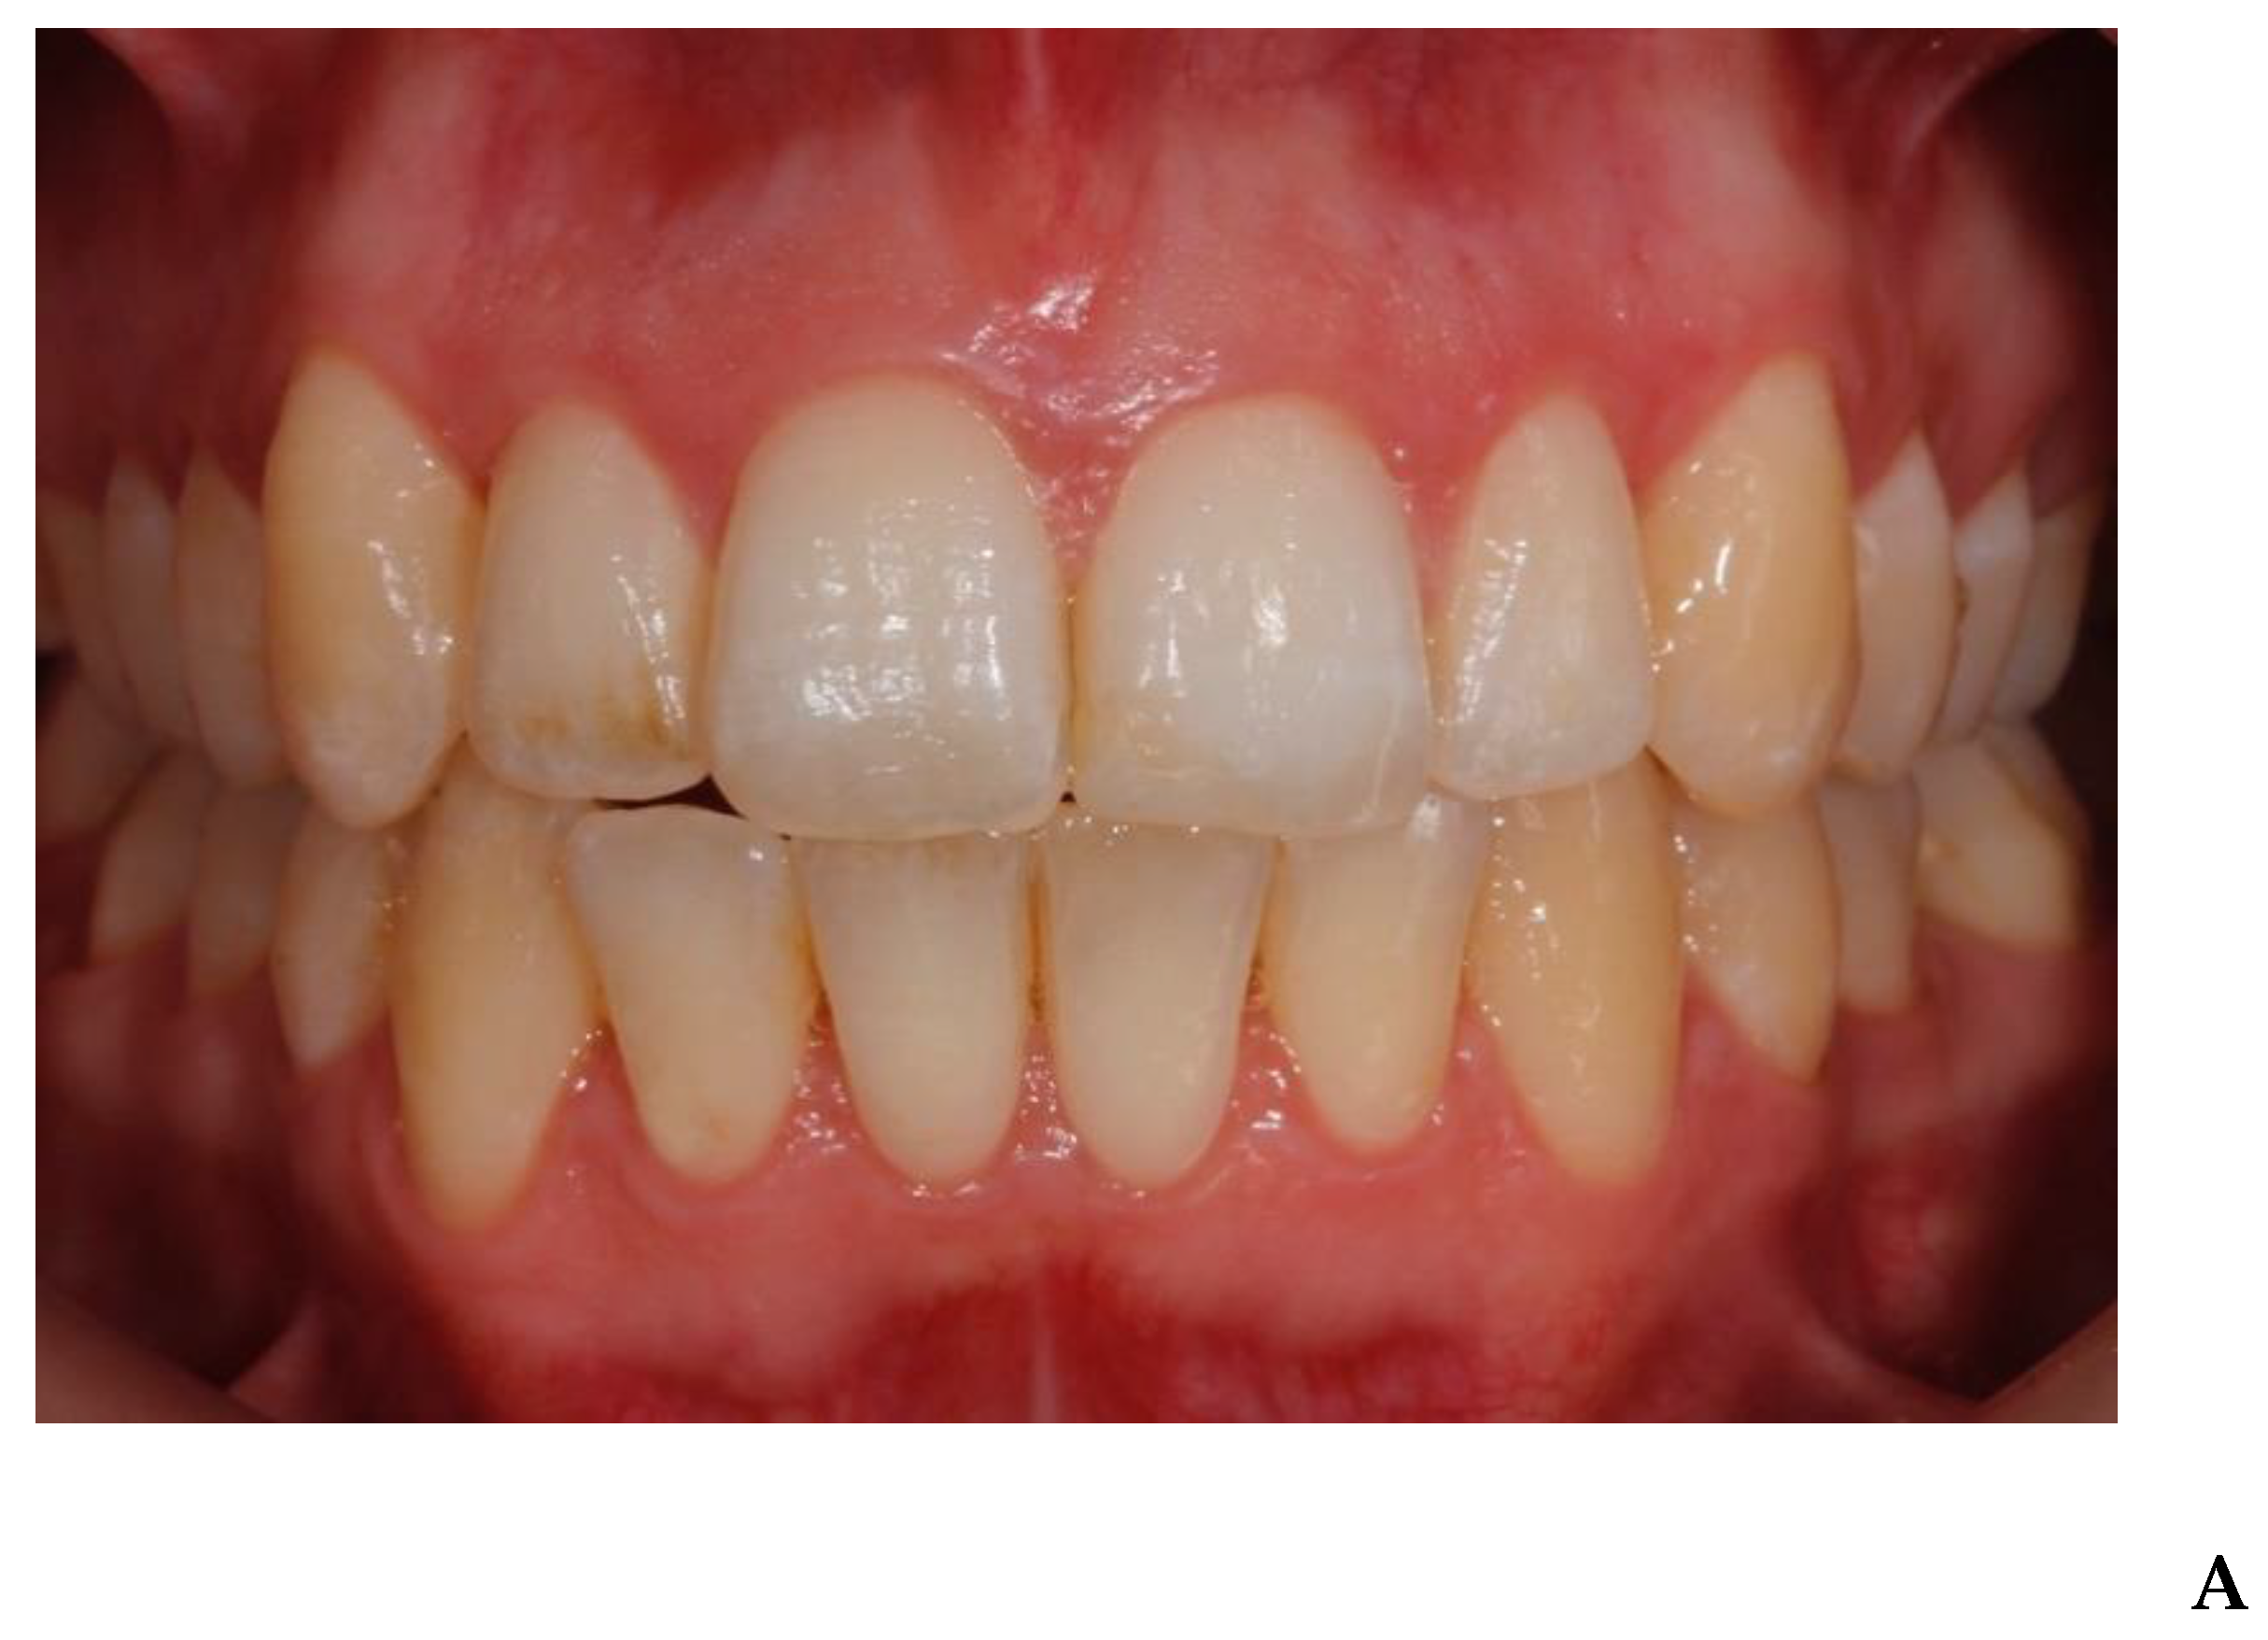

3. Results